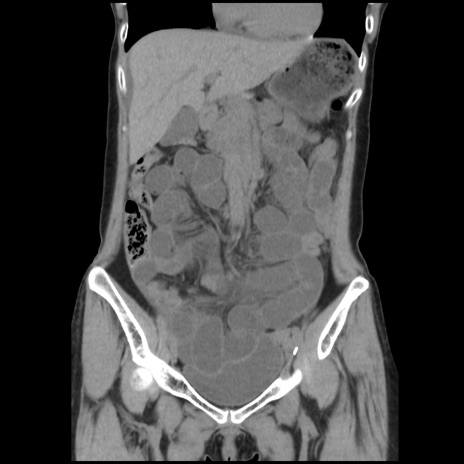

横断像

【症例】40歳代 女性

【主訴】上腹部痛、嘔気・嘔吐

【現病歴】約9時間前頃から急に上腹部痛、嘔気、嘔吐が出現。改善しないため救急要請。

【既往歴】子宮頚癌(広汎子宮全摘術、放射線療法)、腸閉塞

【身体所見】腹部:平坦、軟、腸雑音亢進、上腹部を中心に腹部全体に圧痛あり。

【データ】WBC 8400、CRP 0.03